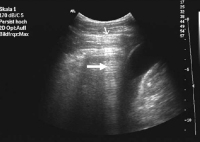

Kolon-Divertikulitis: Diagnostik und sonographisch gesteuerte Therapie

Journal für Gastroenterologische und Hepatologische Erkrankungen 2009; 7 (2): 13-18 Volltext (PDF) Summary Praxisrelevanz Fragen zum Artikel Abbildungen